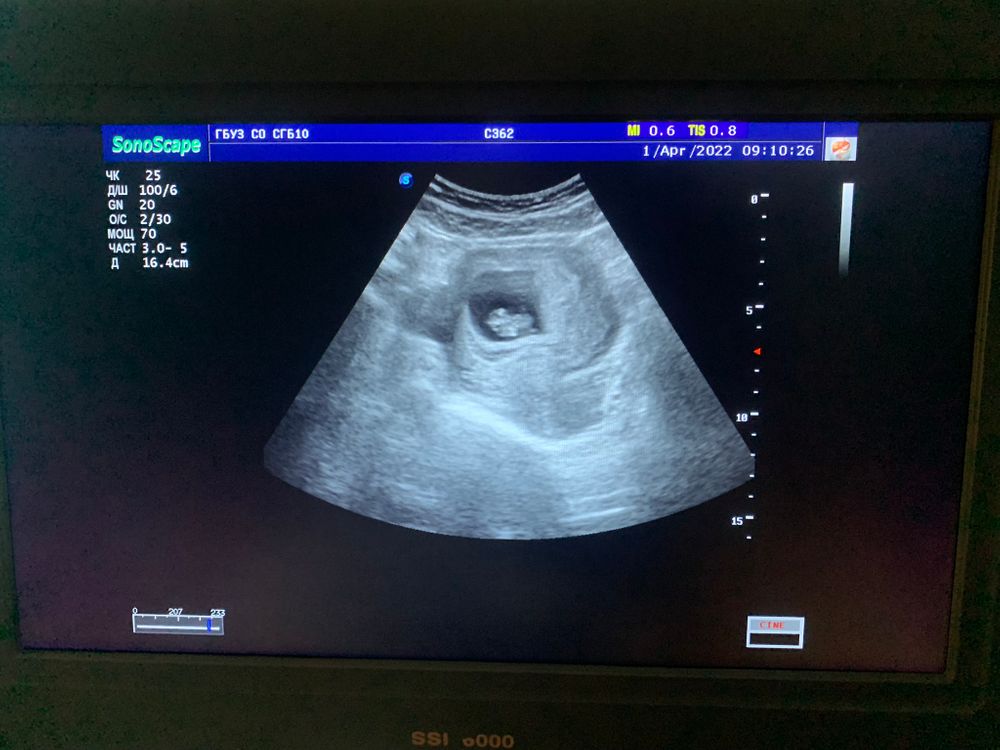

По рамзи девочка) трансвагинальное узи отзеркаливает метод рамзи) если бы сделали через живот узи картинка была бы наоборот)

Nastya Morozova, если слева это шейка матки, а справа дно, то метолу рамзи - девочка)

По рамзи у вас девочка. В первую беременность у меня совпало, а сейчас еще не знаю

Здравствуйте подскажите какой пол у ребёнка? 12 недель На какой неделе узнавали пол малыша?